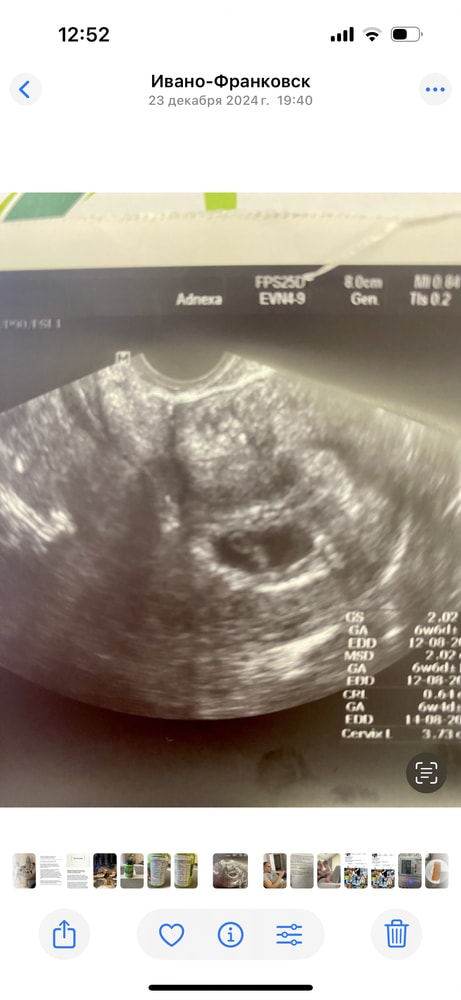

УЗИ, КТГ, доплерВопрос в заголовке. Делала в 6 недель узи трансвагинально и сделала видео для мужа. Посмотрите куда прикрепился и кого ждать?

Ди, знаю что рано, но так хочется девочку. Начиталась про метод Рамзи, теперь разглядываю. Нашла на просторах инета такое фото